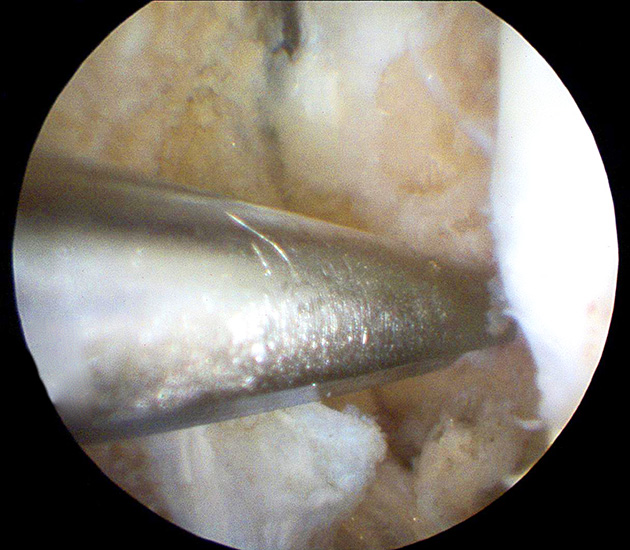

Nachfolgend wird die OP-Technik an einem rechten Sprunggelenk unter Verwendung von PEEK-Ankern veranschaulicht.

Intra- und extraartikuläre Darstellung des Operationsablaufs am linken Sprunggelenk mit selbstschneidenden Titanfadenankern.